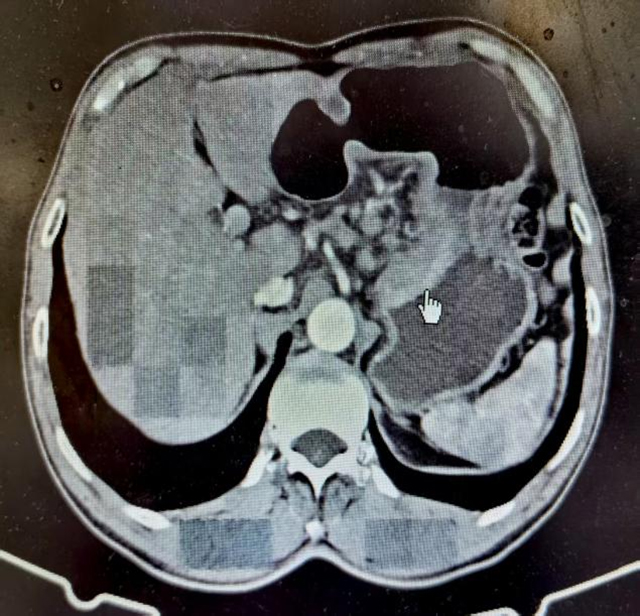

普外·疝与腹壁外科罗伟主治医师接诊后,为黄先生进行了腹部体格检查,全腹部CT提示:胃贲门壁增厚,考虑恶性肿瘤(Ca)可能,肝胃间隙及腹膜后多发淋巴结增大,有一定淋巴结转移概率。经详细询问病史及综合院外检查资料,考虑诊断为“胃底贲门恶性肿瘤”。

完善术前准备后,郭伍斌副教授团队在全麻下实施了腹腔镜全胃切除术,术中,医生们小心翼翼地切除全部胃组织、清扫淋巴结、重建消化道……可见胃底贲门一巨大溃疡型肿块,大小约7*5*2cm,侵及全层胃壁。